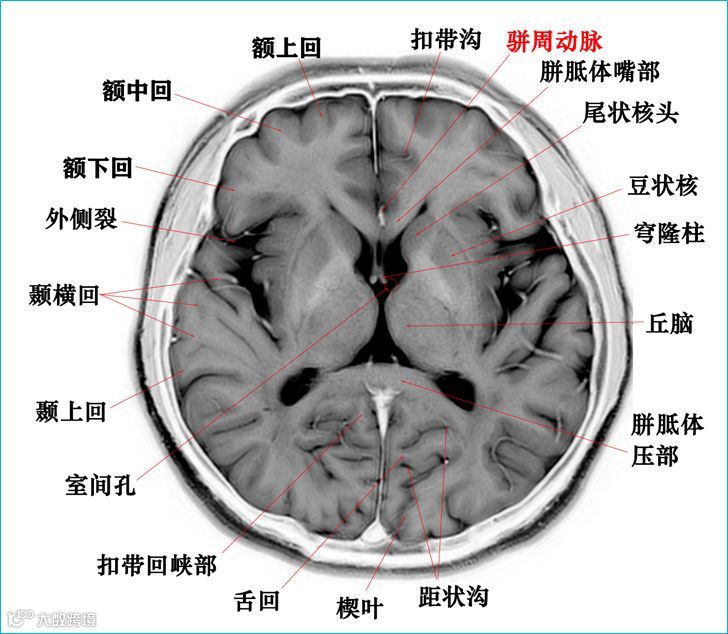

在T2WI反相图学下的颅脑断层解剖(吴晓安老师亲自手动标准)以及标本断层解剖,满满干货,坐在小板凳上,一起学习吧……